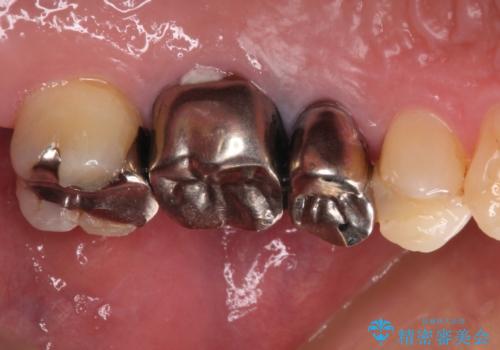

抜歯が必要な小臼歯 インプラントによる補綴治療

- 頻繁に銀歯が外れてしまうとのことで来院された患者様です。

歯肉の中、深いところまでむし歯が進行しており、歯根を部分矯正で引っ張り出してから補綴治療を行うか、抜歯してインプラント補綴治療を行うか選択することになりました。

海外での勤務があり、部分矯正は困難とのことで、インプラントによる補綴治療を行うこととしました。

より審美的で、より機能的に優れた治療をご希望とのことであったので、ジルコニアカスタムアバットメントを用いたインプラント治療を行うこととしました。